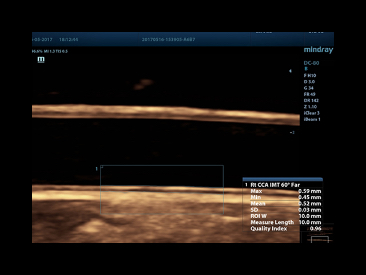

Auto IMT of CCA